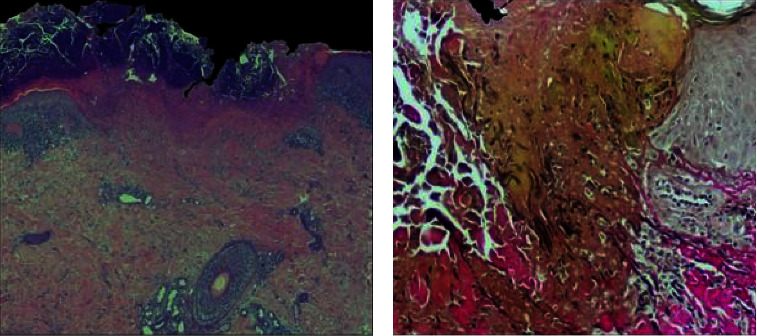

获得性反应性穿孔胶原病是一种罕见的皮肤疾病,其特征是异常结缔组织通过表皮和/或毛囊单位挤出。反应性穿孔性胶原病通常与以瘙痒为常见症状的全身性疾病(如糖尿病和慢性肾病)有关。较少见的是,它与慢性炎症性皮肤病有关,包括特应性皮炎,本病例就是如此。在本报告中,我们描述了一例特殊病例:一名 35 岁的男性患者患有与特应性皮炎相关的获得性反应性穿孔性胶原病,对传统的局部和全身治疗均有抗药性,在使用杜必鲁单抗治疗 12 周后,临床症状和体征完全消失。在我们的患者中,特应性皮炎引起的严重瘙痒很可能导致了获得性穿孔性胶原病病变的发生,这种病变被认为是对慢性搔抓和皮肤反复损伤的反应性反应。众所周知,特应性皮炎的慢性瘙痒是由包括IL-4和IL-13在内的2型细胞因子驱动的,而抑制IL-4和IL-13信号传导的单克隆抗体dupilumab已被证明能有效治疗中度至重度特应性皮炎以及其他2型细胞因子驱动的瘙痒性皮肤病。本病例支持使用杜匹单抗治疗反应性穿孔性皮肤病。

Acquired reactive perforating collagenosis is a rare cutaneous disorder characterised by the extrusion of abnormal connective tissue trough epidermidis and/or follicular units. Reactive perforating collagenosis is often associated with systemic diseases in which pruritus is a common symptom (e.g., diabetes and chronic kidney disease). Less commonly, it has been associated with chronic inflammatory dermatoses, including atopic dermatitis, as in this case. In this report, we describe the exceptional case of a 35-year-old man affected by acquired reactive perforating collagenosis associated with atopic dermatitis who was resistant to conventional topical and systemic treatment and experienced complete resolution of clinical signs and symptoms after 12 weeks of treatment with dupilumab. In our patient, the severe pruritus induced by atopic dermatitis likely contributed to the development of acquired perforating collagenosis lesions, which are thought to be a reactive response to chronic scratching and repetitive injury to the skin. Chronic pruritus in atopic dermatitis is known to be driven by type 2 cytokines, including IL-4 and IL-13, and dupilumab, a monoclonal antibody inhibiting IL-4 and IL-13 signalling, has been shown to be effective in the treatment of moderate to severe atopic dermatitis as well as other type 2-driven pruritic dermatological conditions. This case supports the potential use of dupilumab for the treatment of reactive perforating dermatosis.